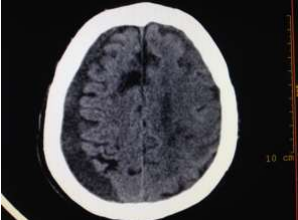

Radiology

Fig 1,2,3,4,5,6,7,8,9,10,11,12,13,14,15

Figure 1